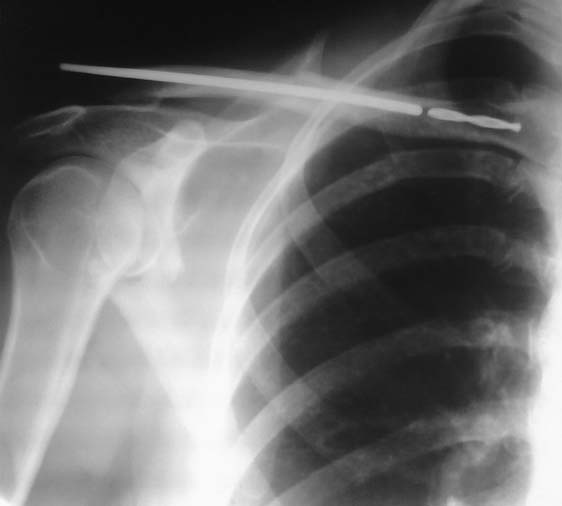

Оставить как есть, учитывая спиральную нарезку сверла, мигрировать не должно.

Рентген в динамике.

А шейка лопатки не сломана?

Нет,с лопаткой всё в порядке..

Конечно сломана!

Очень часто во время операции происходят нестандартные ситуации - потеря салфеток, игл или поломка инструментов. Возникшую ситуацию желательно решить до закрытия раны, и тогда проблема останется в пределах операционной. Поздно обнаруженный технический брак становится проблемой для всех, и во избежание дальнейшего конфликта надо сразу сообщить родственникам или больному. Описание и документирование поможет избежать последующих исков...

Все инородные тела должны удаляться как можно быстро, но в зависимости от локализации и случая, сломанные забытые импланты можно оставить, временно! Это можно в метафизарном отделе, когда метал не создает давление на окружающие ткани, на сосуды или нервы. А также в ситуациях damage control, т.е при ургентных операциях, когда трудоемкий поиск может нанести больший вред. Еще рекомендуется остановить поиск при чрезмерной усталости операционной бригады, что может повлиять на исход.

В данном случае остаток сверла можно удалить после консолидации. Не трогая место перелома с медиальной стороны ключицы, можно сделать передний кортикальный доступ высокоскоростным буром. Желательно TPS от Stryker, 3 мм головкой на переднем кортексе делается продольный паз на ширину сверла, и оно захватывается крючком. Тонкий слой костного воска остановит кровотечение и закроет кортикальный дефект.

А по поводу тактики лечения, на снимке подозрение на перелом шейки лопатки тоже. Возможно, ваш диагноз правильный, но отсутствие перелома лопатки надо подтвердить другими снимками. Односторонние переломы шейки лопатки и ключицы относятся к “floating shoulder” т.е. отсутствует структура, удерживающая конечность в плече. Оторванную от тела верхнюю конечность надо фиксировать, и ключица дает возможность "пристегнуть" конечность к туловищу. Изолированный перелом ключицы не является абсолютным показанием для фиксации, тем более стержнем.